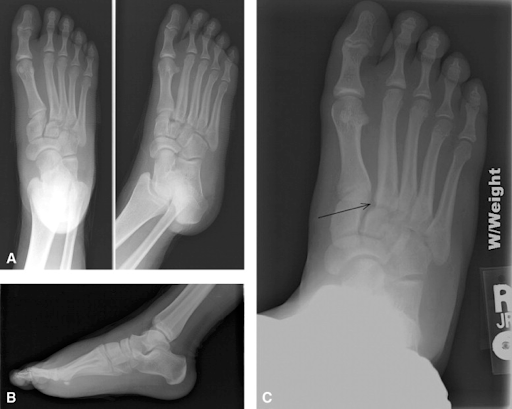

Lisfranc (midfoot) injuries result if bones in the midfoot are broken or ligaments that support the midfoot are torn.

A lisfranc injury, also known as lisfranc fracture, is an injury of the foot in which one or more of the metatarsal bones are displaced from the tarsus. Lisfranc joint injuries are rare, complex and often misdiagnosed. The severity of a lisfranc injury can . The lisfranc joint is the spot on top of your foot where the metatarsal bones (the bridges to . You never want to suffer an injury, but when it happens, you want to have access to excellent medical care and sound legal advice. A lisfranc joint injury is a type of injury to the bones or ligaments, or both, in the middle part of your foot. A direct force often involves something heavy falling on the foot. An accident injury lawyer is one of the first calls you should make after a damaging accident where you weren't at fault.